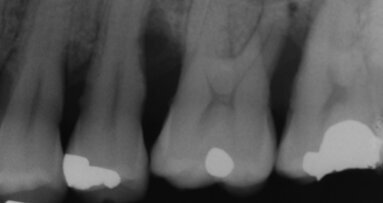

Nella malattia parodontale, la tasca parodontale contiene diverse sostanze che contribuiscono al protrarsi della condizione di malattia (Fig. 5):

1. placca e tartaro sulla superficie del dente;

2. batteri patogeni;

3. un rivestimento epiteliale ulcerato con tessuto di granulazione e sottoprodotti batterici.

1. Il lato di tessuto duro della tasca viene prima trattato con uno scaler a ultrasuoni e con strumentazione manuale (Fig. 6).

4. Il ri-sondaggio dei siti trattati non dovrebbe essere eseguito prima di 3 mesi dopo il trattamento per permettere una corretta guarigione (Fig. 10). Il tessuto rimane fragile per questo periodo di tempo.